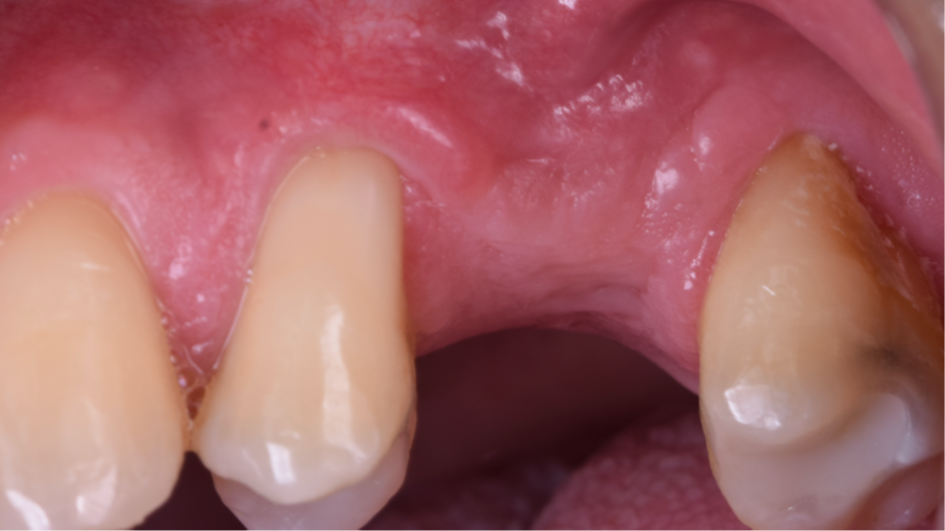

O presente trabalho tem como objetivo fazer um relato de caso clínico de reintervenção em enxerto ósseo para levantamento de seio maxilar pela técnica da janela lateral com instalação simultânea de implante Maestro Superiore.

Relato de Caso